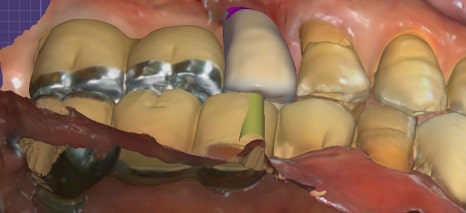

✅ 치료 후 사진

첫번째 사진: 치료 완료 후 파노라마 X-ray입니다. 새로 심은 #15 임플란트와 기존 #17 임플란트를 연결하여 어금니 기능을 회복했습니다.

두번째 사진: 치료 후 구강 내 모습입니다.

앞니 크라운과 어금니 임플란트 보철까지 완성된 상태로, 정확하게 맞물리며 식사 시 불편이 크게 줄어들었습니다.

세번째 사진: 구강스캐너로 촬영한 디지털 보철 디자인 이미지입니다. 모든 보철물은 병원 내 기공실에서 정밀하게 제작되었습니다.

임플란트는 안정적으로 유착되었고, 두 달 후 오른쪽 작은 어금니 임플란트 보철까지 마무리되었습니다.